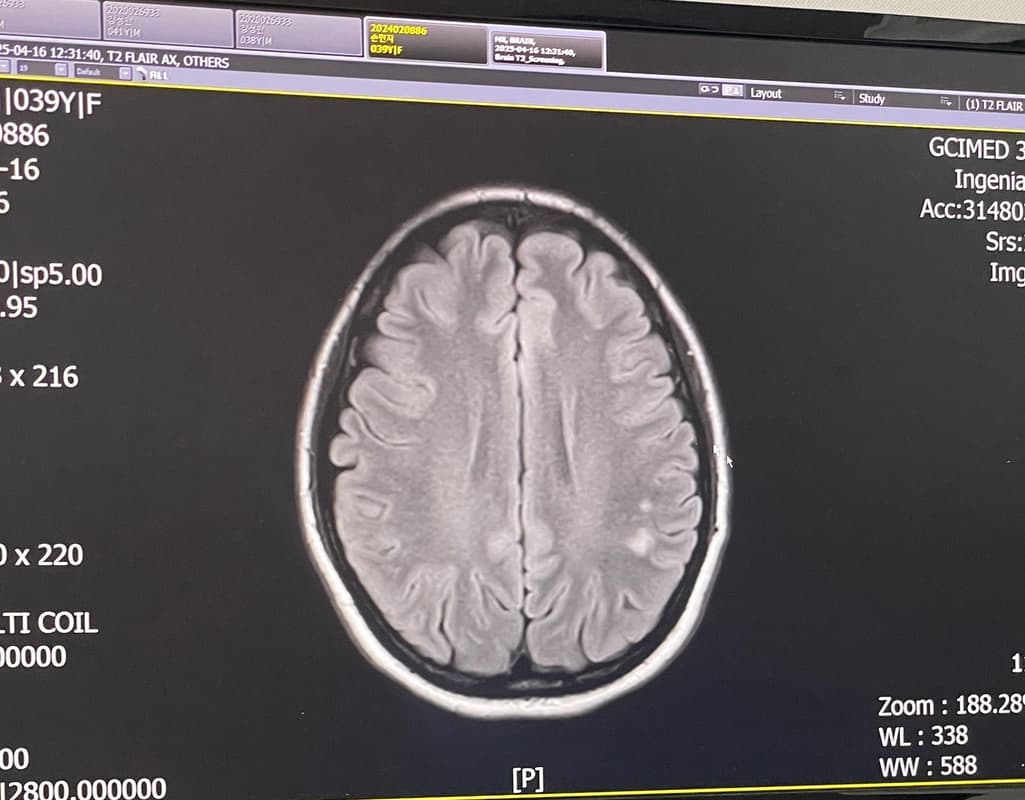

뇌 mri t2 스크리닝- 좌측 두정엽 뇌질 고신호 강도로 소혈관질환 의심 소견

말씀하신 내용만 토대로해서 대답해 드리자면 뇌 MRI에서 "좌측 두정엽 뇌질 고신호 강도"로 소혈관질환 의심 소견이 나왔다는 것은 작은 혈관에 문제가 있을 가능성이 있다는 것을 의미합니다. 일반적으로 이러한 소견은 소혈관성 질환이나 미세혈관 질환에 의해 발생할 수 있으며, 뇌졸중이나 기타 뇌혈관 질환의 전조 증상일 수 있습니다. 하지만, 소견만으로는 급성 질환 여부를 판단하기 어려우므로, 추가적인 검사와 세밀한 평가가 필요해요